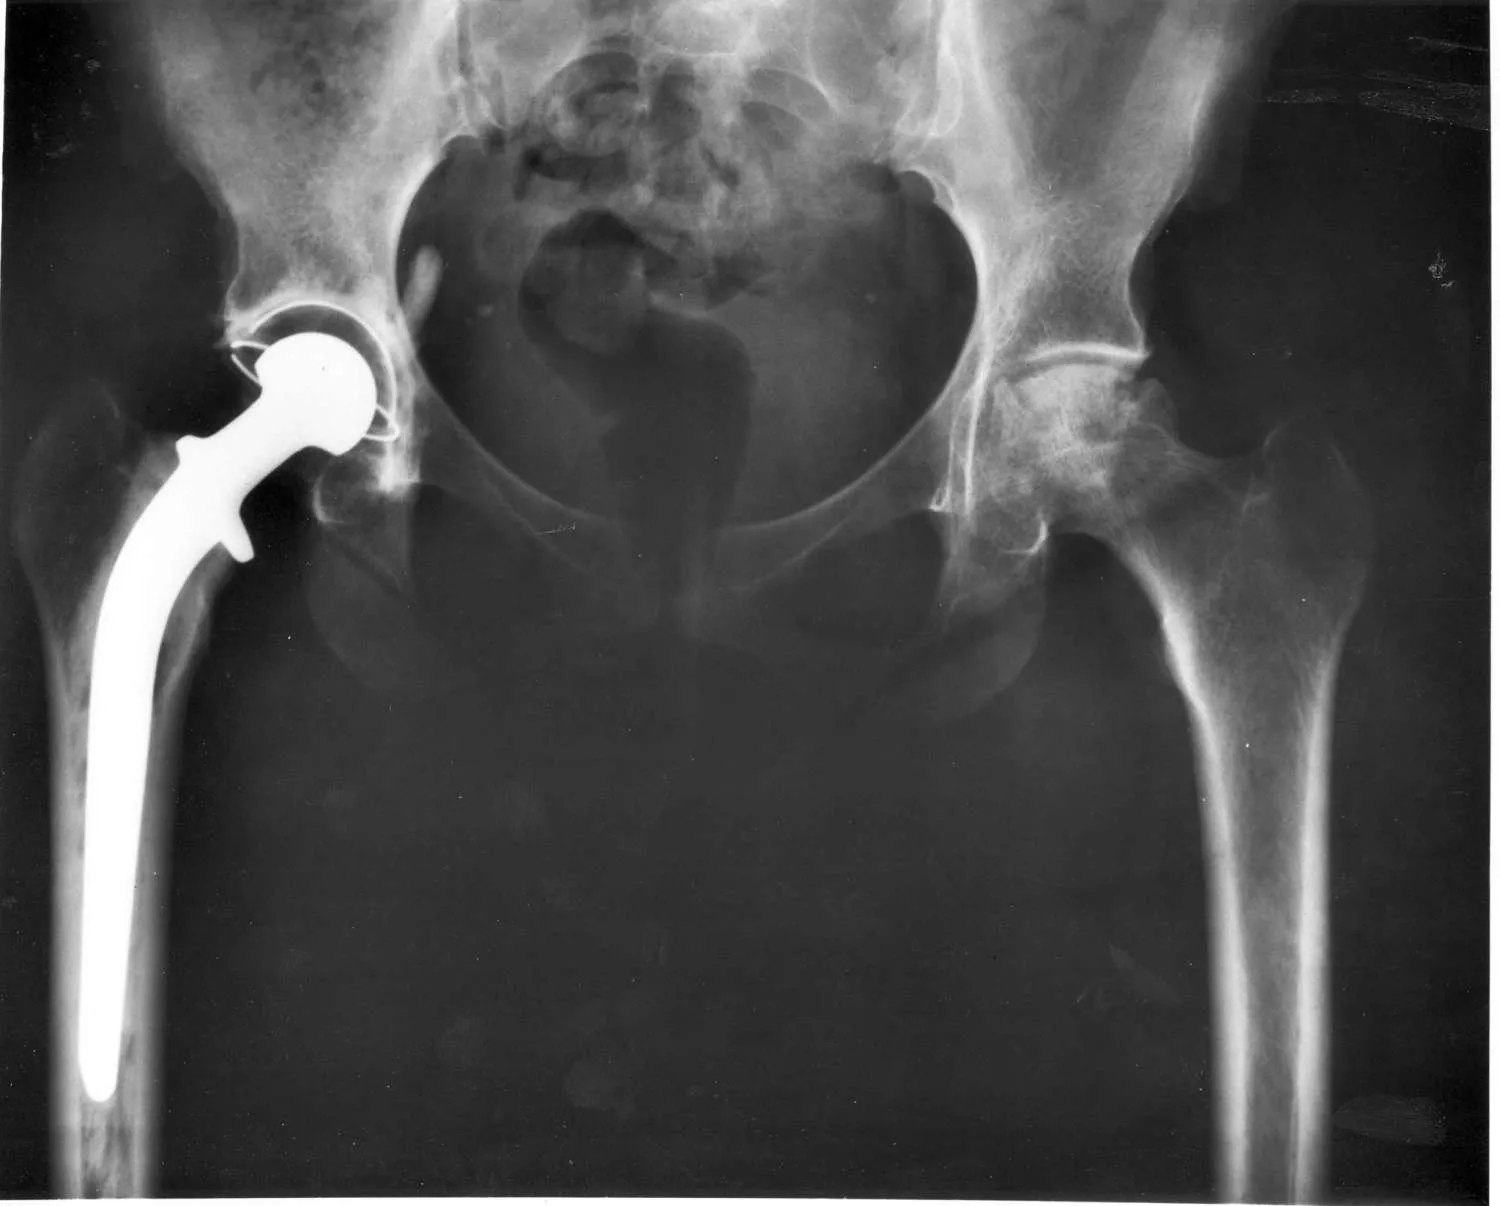

Röntgenfelvétel csípőízületi implantátumról

A teljes csípőprotézis beépítése olyan operáció, melynek során a megbetegedett, károsodott csípőízületet helyettesítik. Kétféle eljárással építik be a protézist; az egyik mód az, amikor a beépítéskor a rögzítéshez speciális komponensű cementet használnak, a másik eljárásnál cement nélkül, egy speciálisan kialakított protézist ültetnek be a károsodott ízület helyére.